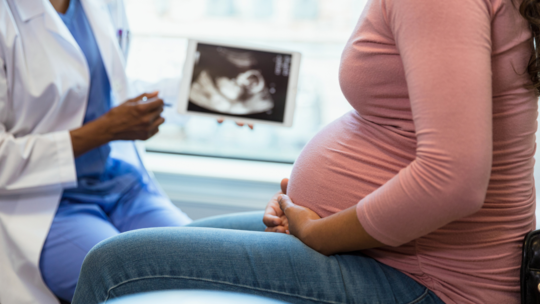

"Common Causes of Miscarriage in Early Pregnancy: What You Should Know\",\"imageid\":\"131009054\",\"imgsize\":\"1661384\",\"lu\":\"May 12, 2026, 02:25 PM\",\"id\":131009054,\"dl\":\"May 11, 2026, 03:00 PM\",\"seolocation\":\"pregnancy/causes-of-miscarriage-in-early-pregnancy\",\"subsecname\":\"Pregnancy\",\"subsecmsid\":112886004,\"syn\":\"It is very natural to experience happiness and a little anxiety simultaneously during the early weeks of pregnancy. Concerns about miscarriage are common, and many causes are not within your control. Learning about these can help you feel more supported.\",\"agency\":{\"id\":87654322},\"tn\":\"news\",\"imgratio\":\"0.5625\",\"dm\":\"t\",\"subsecseolocation\":\"pregnancy\",\"host\":\"prega\",\"slot\":\"10\"},{\"hl\":\"How Often Should You Bathe a Newborn Baby?\",\"imageid\":\"131005010\",\"imgsize\":\"35408\",\"lu\":\"May 11, 2026, 01:00 PM\",\"id\":131005010,\"dl\":\"May 11, 2026, 01:00 PM\",\"seolocation\":\"baby/bathing-newborn-baby-how-often-should-you-do-it\",\"subsecname\":\"Baby\",\"subsecmsid\":113631885,\"syn\":\"Bathing your newborn can feel both special and a little overwhelming, especially if you are unsure how often to bathe them. Fortunately, newborns do not require everyday bathing. You can take care of your baby's sensitive skin, make bathing time a peaceful experience, and create a bonding experience by knowing the proper frequency and using safe, gentle bathing techniques.\",\"agency\":{\"id\":87654322},\"tn\":\"news\",\"imgratio\":\"0.5625\",\"dm\":\"t\",\"subsecseolocation\":\"baby\",\"host\":\"prega\",\"slot\":\"11\"},{\"hl\":\"Blood Clots During Pregnancy: Understanding the Risks and Complications\",\"imageid\":\"131002969\",\"imgsize\":\"1495735\",\"lu\":\"May 11, 2026, 11:00 AM\",\"id\":131002969,\"dl\":\"May 11, 2026, 11:00 AM\",\"seolocation\":\"pregnancy/blood-clots-during-pregnancy-risks-symptoms-prevention\",\"subsecname\":\"Pregnancy\",\"subsecmsid\":112886004,\"syn\":\"Blood clots during pregnancy are a serious matter, but the positive part is that they are uncommon and usually preventable with proper awareness and care. Many expectant parents worry about this issue because pregnancy naturally changes how the blood behaves. But understanding the facts helps you stay safe and enjoy this special time.\",\"agency\":{\"id\":87654322},\"tn\":\"news\",\"imgratio\":\"0.5625\",\"dm\":\"t\",\"subsecseolocation\":\"pregnancy\",\"host\":\"prega\",\"slot\":\"12\"},{\"hl\":\"IVF Complications: What Every Couple Should Prepare For\",\"imageid\":\"130957503\",\"imgsize\":\"1771006\",\"lu\":\"May 11, 2026, 09:00 AM\",\"id\":130957503,\"dl\":\"May 11, 2026, 09:00 AM\",\"seolocation\":\"getting-pregnant/ivf-complications-symptoms-and-risks\",\"subsecname\":\"Getting Pregnant\",\"subsecmsid\":112886008,\"syn\":\"In vitro fertilisation (IVF) offers real hope to many couples facing infertility challenges. While the procedure has become much safer over the years, it still carries certain risks and possible complications. Understanding these helps you prepare better and stay alert during the journey.\",\"agency\":{\"id\":87654322},\"tn\":\"news\",\"imgratio\":\"0.5625\",\"dm\":\"t\",\"subsecseolocation\":\"getting-pregnant\",\"host\":\"prega\",\"slot\":\"13\"},{\"hl\":\"Cervical Incompetence: The Silent Cause of Second Trimester Loss\",\"imageid\":\"130956971\",\"imgsize\":\"1233562\",\"lu\":\"May 08, 2026, 07:00 PM\",\"id\":130956971,\"dl\":\"May 08, 2026, 07:00 PM\",\"seolocation\":\"pregnancy/cervical-incompetence-second-trimester-loss\",\"subsecname\":\"Pregnancy\",\"subsecmsid\":112886004,\"syn\":\"For many women, this is their first encounter with a condition called cervical incompetence, and tragically, it often announces itself only after a loss. This walks you through what it is, why it happens silently, how it's diagnosed, and what treatments and monitoring options exist to protect your next pregnancy.\",\"agency\":{\"id\":87654322},\"tn\":\"news\",\"imgratio\":\"0.5625\",\"dm\":\"t\",\"subsecseolocation\":\"pregnancy\",\"host\":\"prega\",\"slot\":\"14\"},{\"hl\":\"Can You Plan a Pregnancy After Recovering From Cancer?\",\"imageid\":\"130956443\",\"imgsize\":\"1165295\",\"lu\":\"May 08, 2026, 05:00 PM\",\"id\":130956443,\"dl\":\"May 08, 2026, 05:00 PM\",\"seolocation\":\"getting-pregnant/pregnancy-planning-after-cancer-treatment\",\"subsecname\":\"Getting Pregnant\",\"subsecmsid\":112886008,\"syn\":\"Planning pregnancy after cancer recovery is possible for many individuals with proper medical guidance. Learn about fertility considerations, safe timing, and expert recommendations to help you make informed, confident decisions about stepping into parenthood.\",\"agency\":{\"id\":87654322},\"tn\":\"news\",\"imgratio\":\"0.5625\",\"dm\":\"t\",\"subsecseolocation\":\"getting-pregnant\",\"host\":\"prega\",\"slot\":\"15\"}]}]}]]\n"])